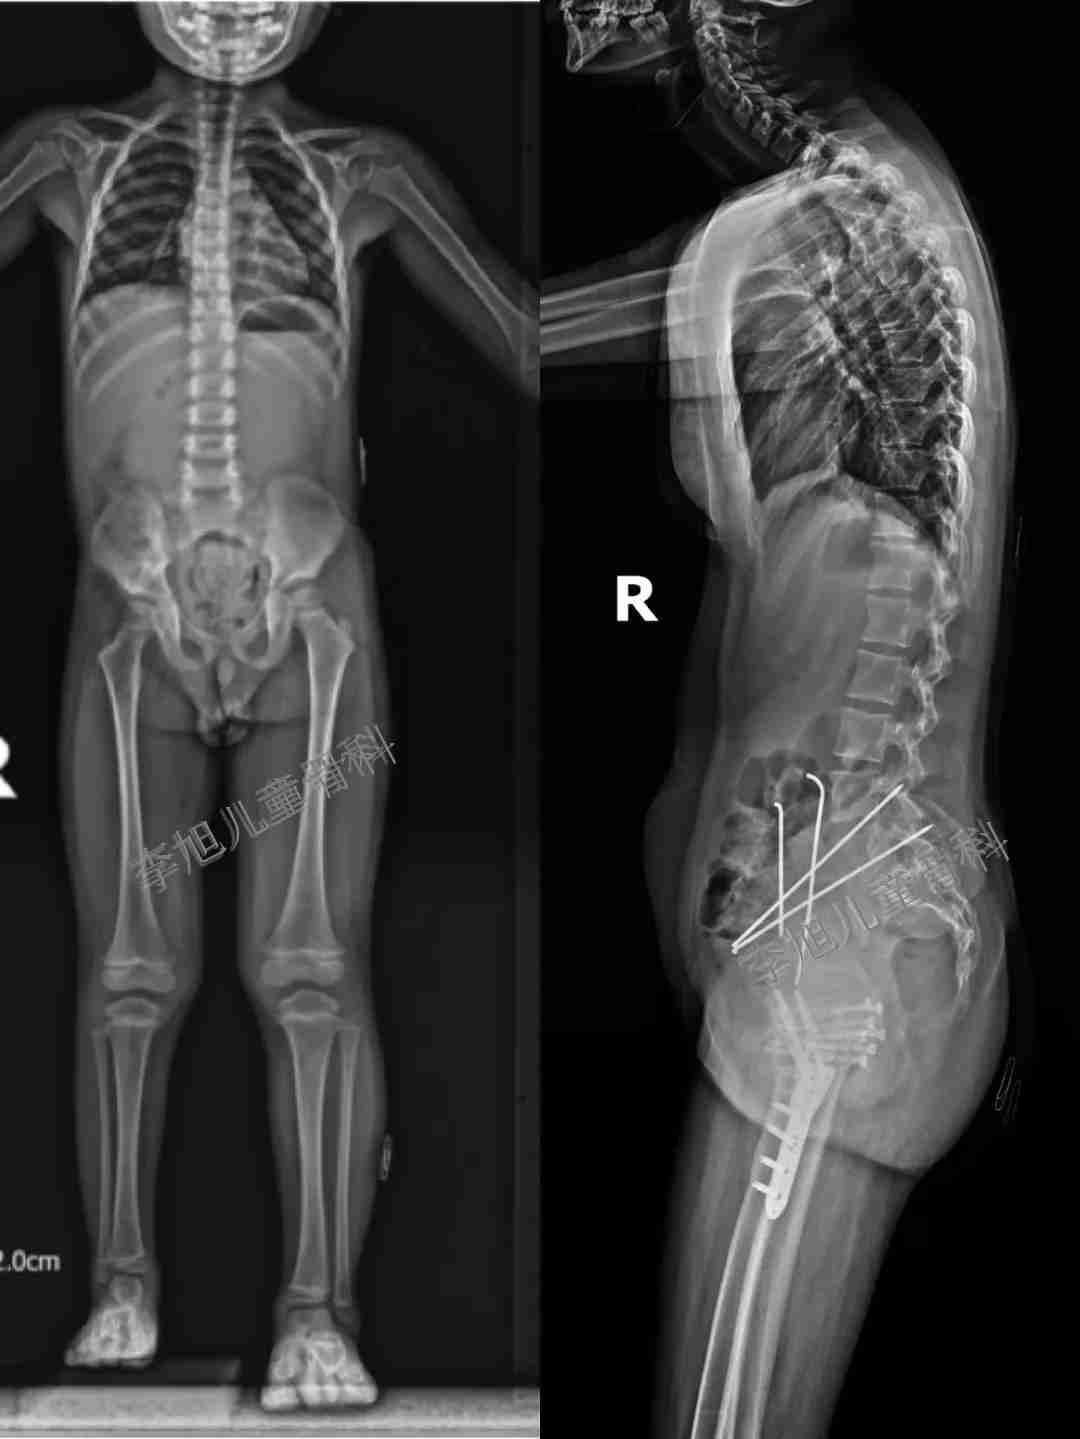

2. 除了上面说的站立位的片子,我们还要求多种体位的拍片评估,而这样的片子往往是目前国内绝大多数医院都无法做到的,比如下面的片子。

我们不但要判断髋关节是否会对脊柱造成影响,更要评估孩子的侧面(矢状面)是否会存在失平衡问题。